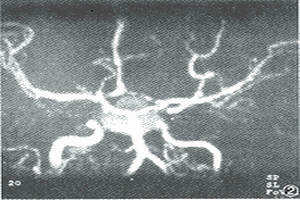

鑑別(1)蛛網膜下腔出血:蛛網膜下腔出血多由顱內動脈瘤破裂或動靜脈血管畸形引起,表現為突然出現的劇烈頭痛,伴嘔吐、意識障礙及腦膜刺激征,與垂體卒中極為相似。但本病發展較垂體卒中為快,從頭痛到意識障礙的時間很短,腰椎穿刺顯示血性腦脊液,CT掃描顯示腦池、腦裂內積血但無蝶鞍占位。不過,垂體卒中時血液亦可進入蛛網膜下腔,但很罕見,且進入的血液量遠較原發性蛛網膜下腔出血為少。

(1)動脈瘤破裂:動脈瘤自頭痛開始至意識喪失發展更為迅速,且易再出血,視神經及動眼神經麻痹常為單側性,無內分泌症狀,蛛網膜下腔出血量也比垂體卒中多。動脈造影有助鑑別。